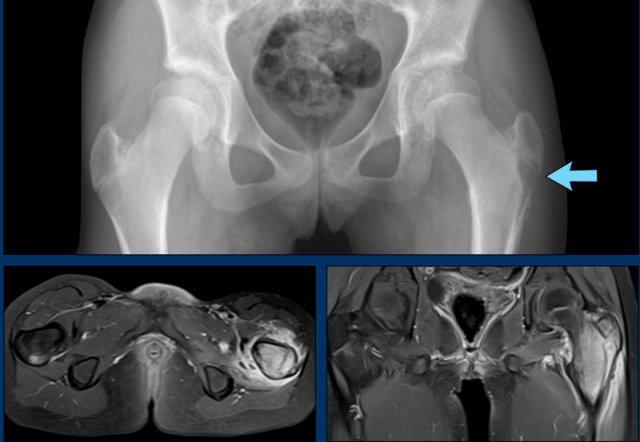

Hình ảnh X-quang khung chậu của bệnh nhân viêm khớp do lao tại khớp háng trái.

Có hẹp khe khớp kín đáo kèm theo xơ cứng dưới sụn tại khớp háng trái.

Các dấu hiệu X-quang này không đặc hiệu và rất có thể là biểu hiện của thoái hóa khớp.

Tiếp tục xem hình ảnh MRI…

Điều bất ngờ với tất cả mọi người là có nhiều ổ áp-xe.

Khi hình thành áp-xe lan rộng như vậy trong khi biểu hiện lâm sàng lại tối thiểu, cần luôn nghĩ đến viêm khớp do lao.

Chẩn đoán viêm khớp do lao được xác lập bằng chọc hút dịch khớp.